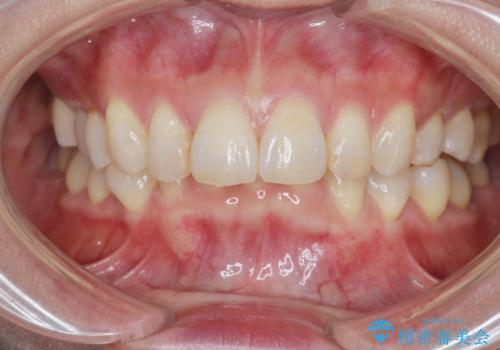

インビザラインで行う前歯のみの部分矯正

- 長年気になっていた前歯の歯並びを改善したいと、矯正治療を希望され思い切って来院されました。

費用と期間を相談し、「気になっているのは前歯だけ。」とのことでしたので前歯のがたつきのみをインビザラインで改善する矯正治療の計画を立てます。

しっかりとマウスピースの装用時間を守っていただき、非常にスムーズに治療を終了することができました。